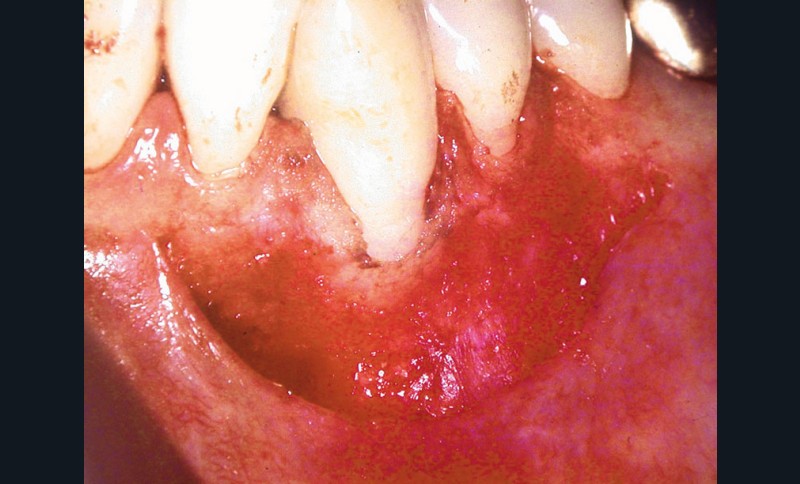

Cas clinique 2

Dans ce deuxième cas, la canine mandibulaire présente également une absence de gencive attachée, associée ici à une récession gingivale (fig. 3).

Une greffe épithélio-conjonctive est réalisée (fig. 4).

Positionnée plus coronairement que la précédente (fig. 5), elle permettra de recouvrir la récession et de recréer un lambeau de gencive attachée (fig. 6).